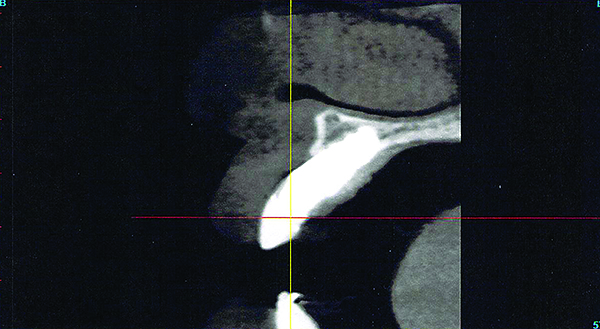

Computerized axial view of the implant in Fig 5 showing the buccal bone loss and exposed implant surface.

Figure 6